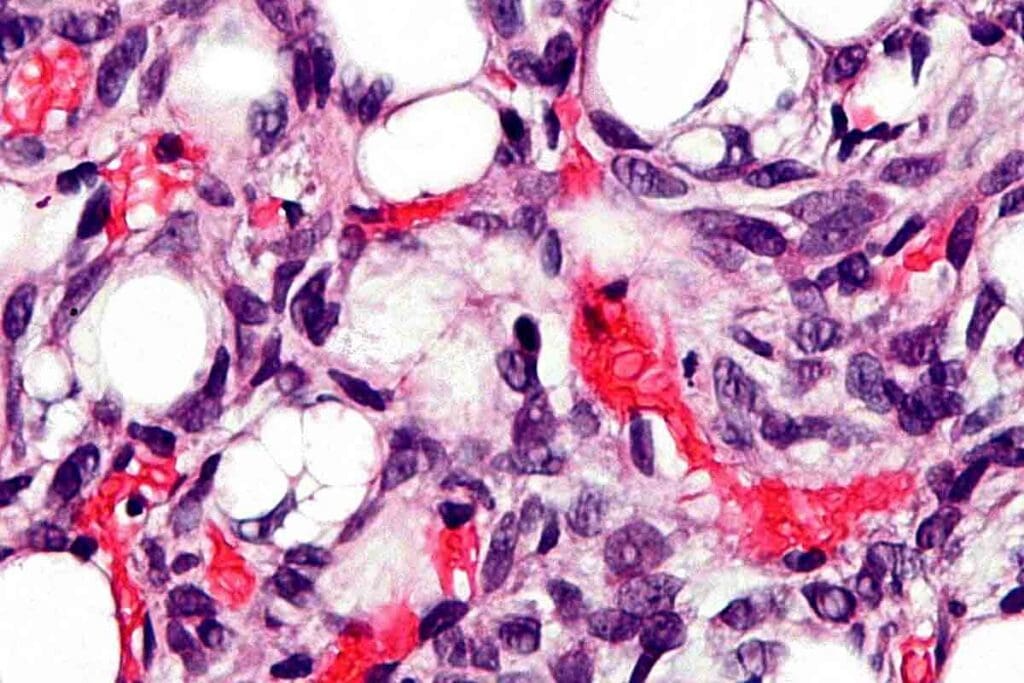

Hematological Changes and Adaptations

Iron deficiency anemia causes changes in blood. Red blood cells get smaller, and hemoglobin levels fall. The body tries to adjust with different strategies.